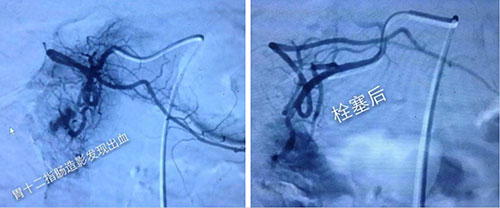

与此同时孔婉楠分别给护士长、主任打电话,汇报了抢救情况。陈安良主任、何永健副主任医师、孙涛医师、孙霖静护士立即从家中赶来,指挥和参加抢救。快速补液、止血、输血等抢救措施。血库在供血的同时,为保证抢救患者的血液供应,又紧急与北京市中心血站联系取血。患者此时血压升至110/60mmhg,意识仍模糊。陈主任立即组织胸外科马振东主任、消化科王铁汉主任等相关科室专家紧急会诊。经过讨论,大家根据患者的出血情况,考虑出血仍在继续,且为动脉出血,关键是要立即止血,于是决定为患者采用DSA下介入栓塞治疗。

在征得患者家属同意后,医务人员迅速行动,立即联系导管室开放绿色通道,由陈安良主任、何永健、刘庆顺大夫在导管室同仁的配和下,快速准确的找到出血点——胃动脉出血,何永健医生成功地实施了栓塞术,血止住了。这时,已经忘却了时间和疲劳的医务人员的脸上才露出了胜利的笑容。观察患者生命体征平稳后,将其安全送回病房,至下午四点半左右,患者无再次出血发生,宣布抢救成功。